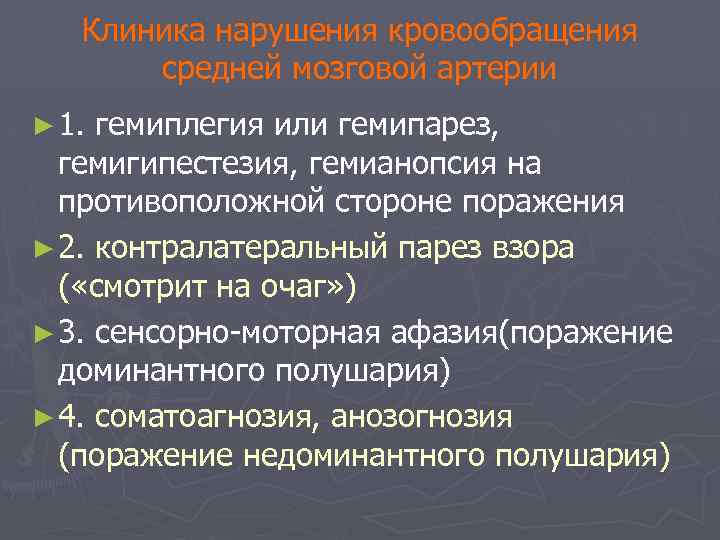

Клиника нарушения кровообращения средней мозговой артерии ► 1. гемиплегия или гемипарез, гемигипестезия, гемианопсия на противоположной стороне поражения ► 2. контралатеральный парез взора ( «смотрит на очаг» ) ► 3. сенсорно-моторная афазия(поражение доминантного полушария) ► 4. соматоагнозия, анозогнозия (поражение недоминантного полушария)